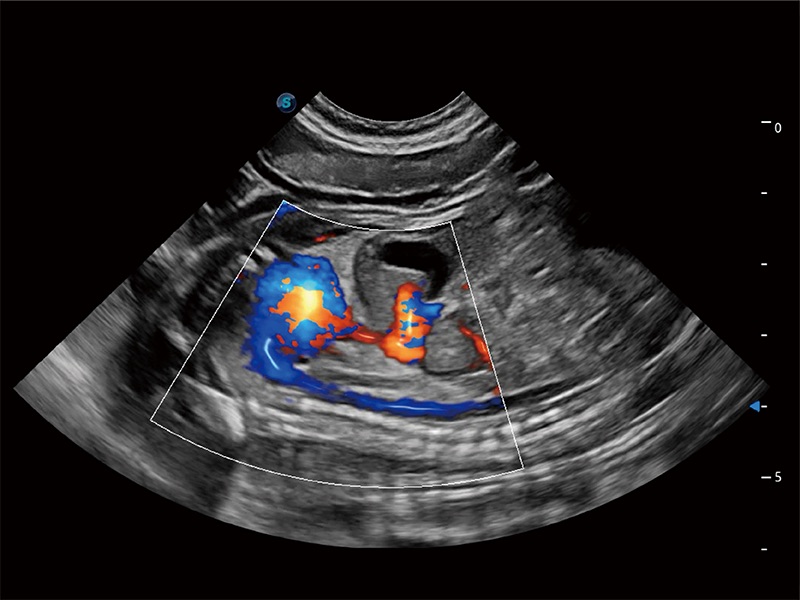

ProPet 80 配备了丰富的心脏探头群、先进的成像技术和专业的心脏测量工具,可帮助动物医生为不同体型和生理结构的动物提供心脏和心肌功能的全面评估。

实时用颜色表示心肌组织运动,观察和定量组织的运动情況,对快速检测与评估心肌的灌注和活性、电传导及心肌收缩和舒张功能等均能提供重要的诊断信息。

通过360度任意调节3条M型取样线,在同一心动周期上观察心脏不同位置的运动曲线,得到准确的心功能测量数据,有效评估心肌运动及左心室功能。